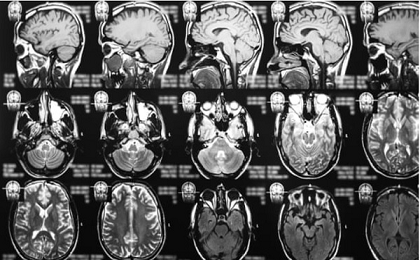

Hai bệnh nhân ung thư não có nguy cơ tử vong đã phản ứng tốt sau khi được thử nghiệm điều trị kết hợp bằng hai loại thuốc miễn dịch. Trong một trường hợp, khối u dường như đã biến mất.